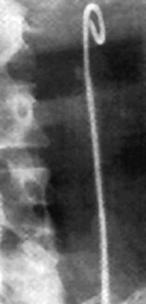

Трансуретральная катетеризация и стентирование почки используются для ретроградного разрешения обструкции верхних мочевых путей, при длительном стоянии камня мочеточника “на месте” или для его смещения для ДЛТ в лоханку (повышается эффективность ДЛТ). Отдельным показанием для установки внутреннего стента являются крупные, множественные и коралловидные камни нормально функционирующей почки, которые могут быть подвергнуты ДЛТ на фоне внутреннего дренирования.

Мочеточниковый стент - специально разработанная трубка, сделанная из гибкого пластикового материала, который помещается в мочеточник, позволяя осуществлять так называемое “закрытое дренирование” мочевых путей.

Длина стента варьирует от 24 до 30 см. Стенты разработаны специально для расположения их в мочевой системе. Верхние и нижние части стента имеют закругления - завитки не позволяющие ему смещаться. Обычно стент устанавливают под наркозом, используя специальный инстумент - цистоскоп или уретероскоп, который проводится в мочевой пузырь через уретру - мочеиспускательный канал.

Стентирование мочевыводящих путей